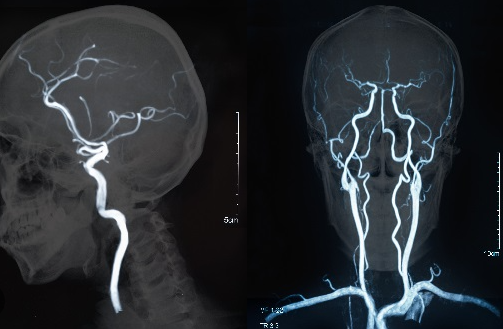

신경과 전문의는 파킨슨병 진단에 필요한 여러 검사와 임상적 평가를 통해 정확한 진단을 내릴 수 있습니다. 진단을 위해 MRI나 CT 스캔과 같은 영상학적 검사가 필요할 수 있으며, 도파민 수송체 스캔(DaTscan)과 같은 특수 검사도 진행될 수 있습니다.